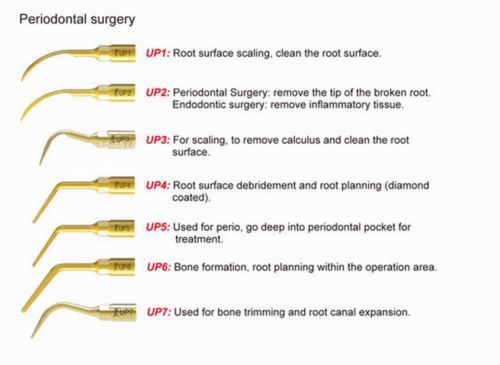

1* Periodontal Surgery Tip UP1 Fit WP Ultrasurgery Metron Piezo Original kla

10* Woodpecker Scaler Periodontics Tip PS4 Scaler Handpiece Original KOLA kla

5* Periodontal Surgery Tip UP5 WP Ultrasurgery Metron Piezosurgery Original kla